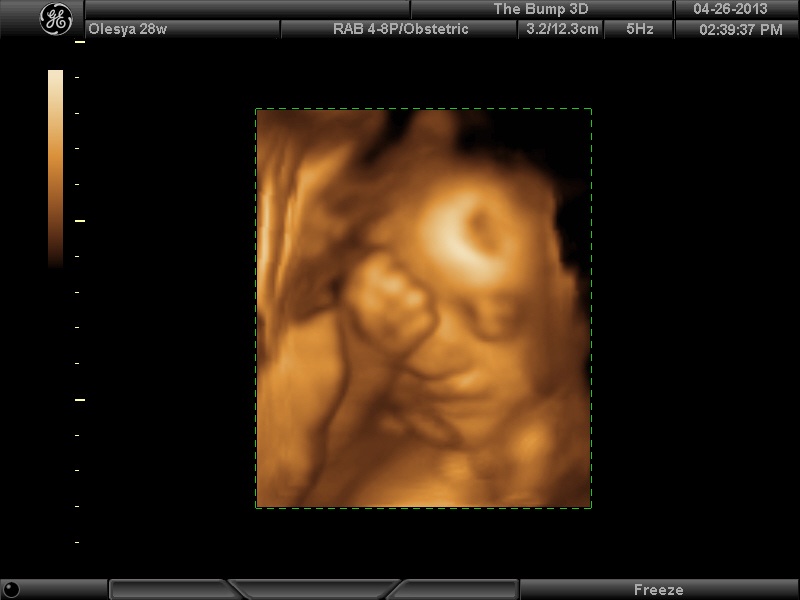

| Еще одна Джианнка:

| Вложения: |

|  KENZEL,OLESYA_5.JPG [ 60.02 КБ | Просмотров: 1246 ]